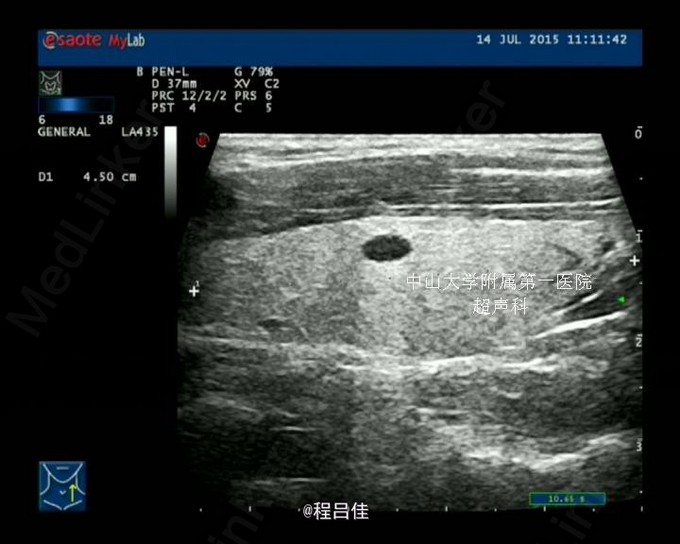

查体: 1.T37℃, P90次/分,R20次/分,BP120/80mmHg。颈软,外形对称,未见颈静脉怒张,未见血管搏动,气管偏左。右侧甲状腺II度肿大,内扪及数个结节,质硬,边界不清,无压痛,随吞咽上下移动。左侧(-)。颈部淋巴结未扪及。突眼征(-),双手震颤试验(-)。 辅查: 甲工5项正常、肺肿瘤组合(-)、血清降钙素原PCT1.31 ng/mL ↑ 、术后钙Ca 1.83 mmol/L ↓ 2.甲状腺US: 右叶甲状腺CA,向胸骨后延伸并侵犯右侧颈静脉起始段;左叶甲状腺滤泡囊肿。 双侧颈部未见异常肿大淋巴结。 3.胸片: 右上纵隔增宽,气管受压向左侧移位 4.心脏彩超:二尖瓣前叶脱垂并关闭不全(轻微),右房近上腔静脉入口处团块状回声。 5.PET-CT:甲状腺右叶及峡部肿块(向下延伸至胸骨上缘水平,邻近气管受压),代谢活跃,考虑恶性肿瘤,右侧颈内及购买起始段、右头臂静脉、上腔静脉、右心房上部节段性代谢增高,考虑癌栓形成。甲状腺左叶小结节,代谢未见异常,考虑结节性甲状腺肿或小囊肿。 6.术中冰冻快速切片报告: (左侧甲状腺)送检3.5x2.5x2cm暗红组织一块,切面暗红,无明显结节。冰冻快速切片报告镜下:结节性甲状腺肿,未见肿瘤。